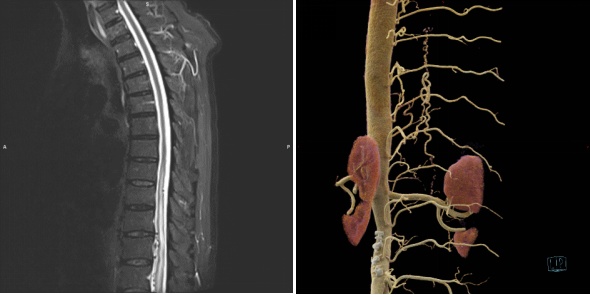

核磁共振图像(左)和光子CT图像(右)

影像学检查是确诊sDAVF的关键手段。以往通常会先通过核磁共振显示脊髓内部的异常信号和血管扩张,再通过脊髓血管造影确定瘘口位置,但需要一点点排查整个脊髓,费时费力,且时而由于血管直径太细无法顺利完成。瑞金医院最新引进的光子CT有着高达110微米的空间分辨率,高分辨率的三维影像可以帮助更精确定位瘘口。果然,在光子CT和脊髓血管造影的高效检查下,清晰定位了王伯瘘口位置,为治疗提供依据。